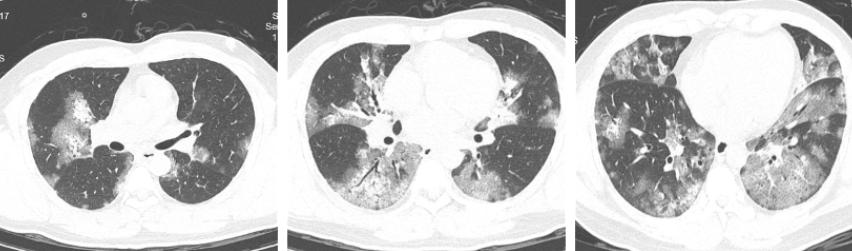

又过了几天,刘先生不仅咳嗽咳痰没有改善,还出现了气急的情况。到医院检查后发现自己感染了甲型流感,但他的胸部CT让接诊医生意识到这不仅仅是普通的流感这么简单。刘先生的两肺都有非常严重的磨玻璃样渗出,也就是平时所说的“白肺”。

治疗前胸部CT(两肺弥漫性磨玻璃样渗出)(图片来源:钱江晚报)

在医护人员的努力下,刘先生的病情逐渐稳定,高烧消退,胸闷气急的症状也得到了缓解。再次复查胸部CT,两肺的炎性渗出都有不同程度的吸收。经过这次大病,刘先生感觉重获新生。